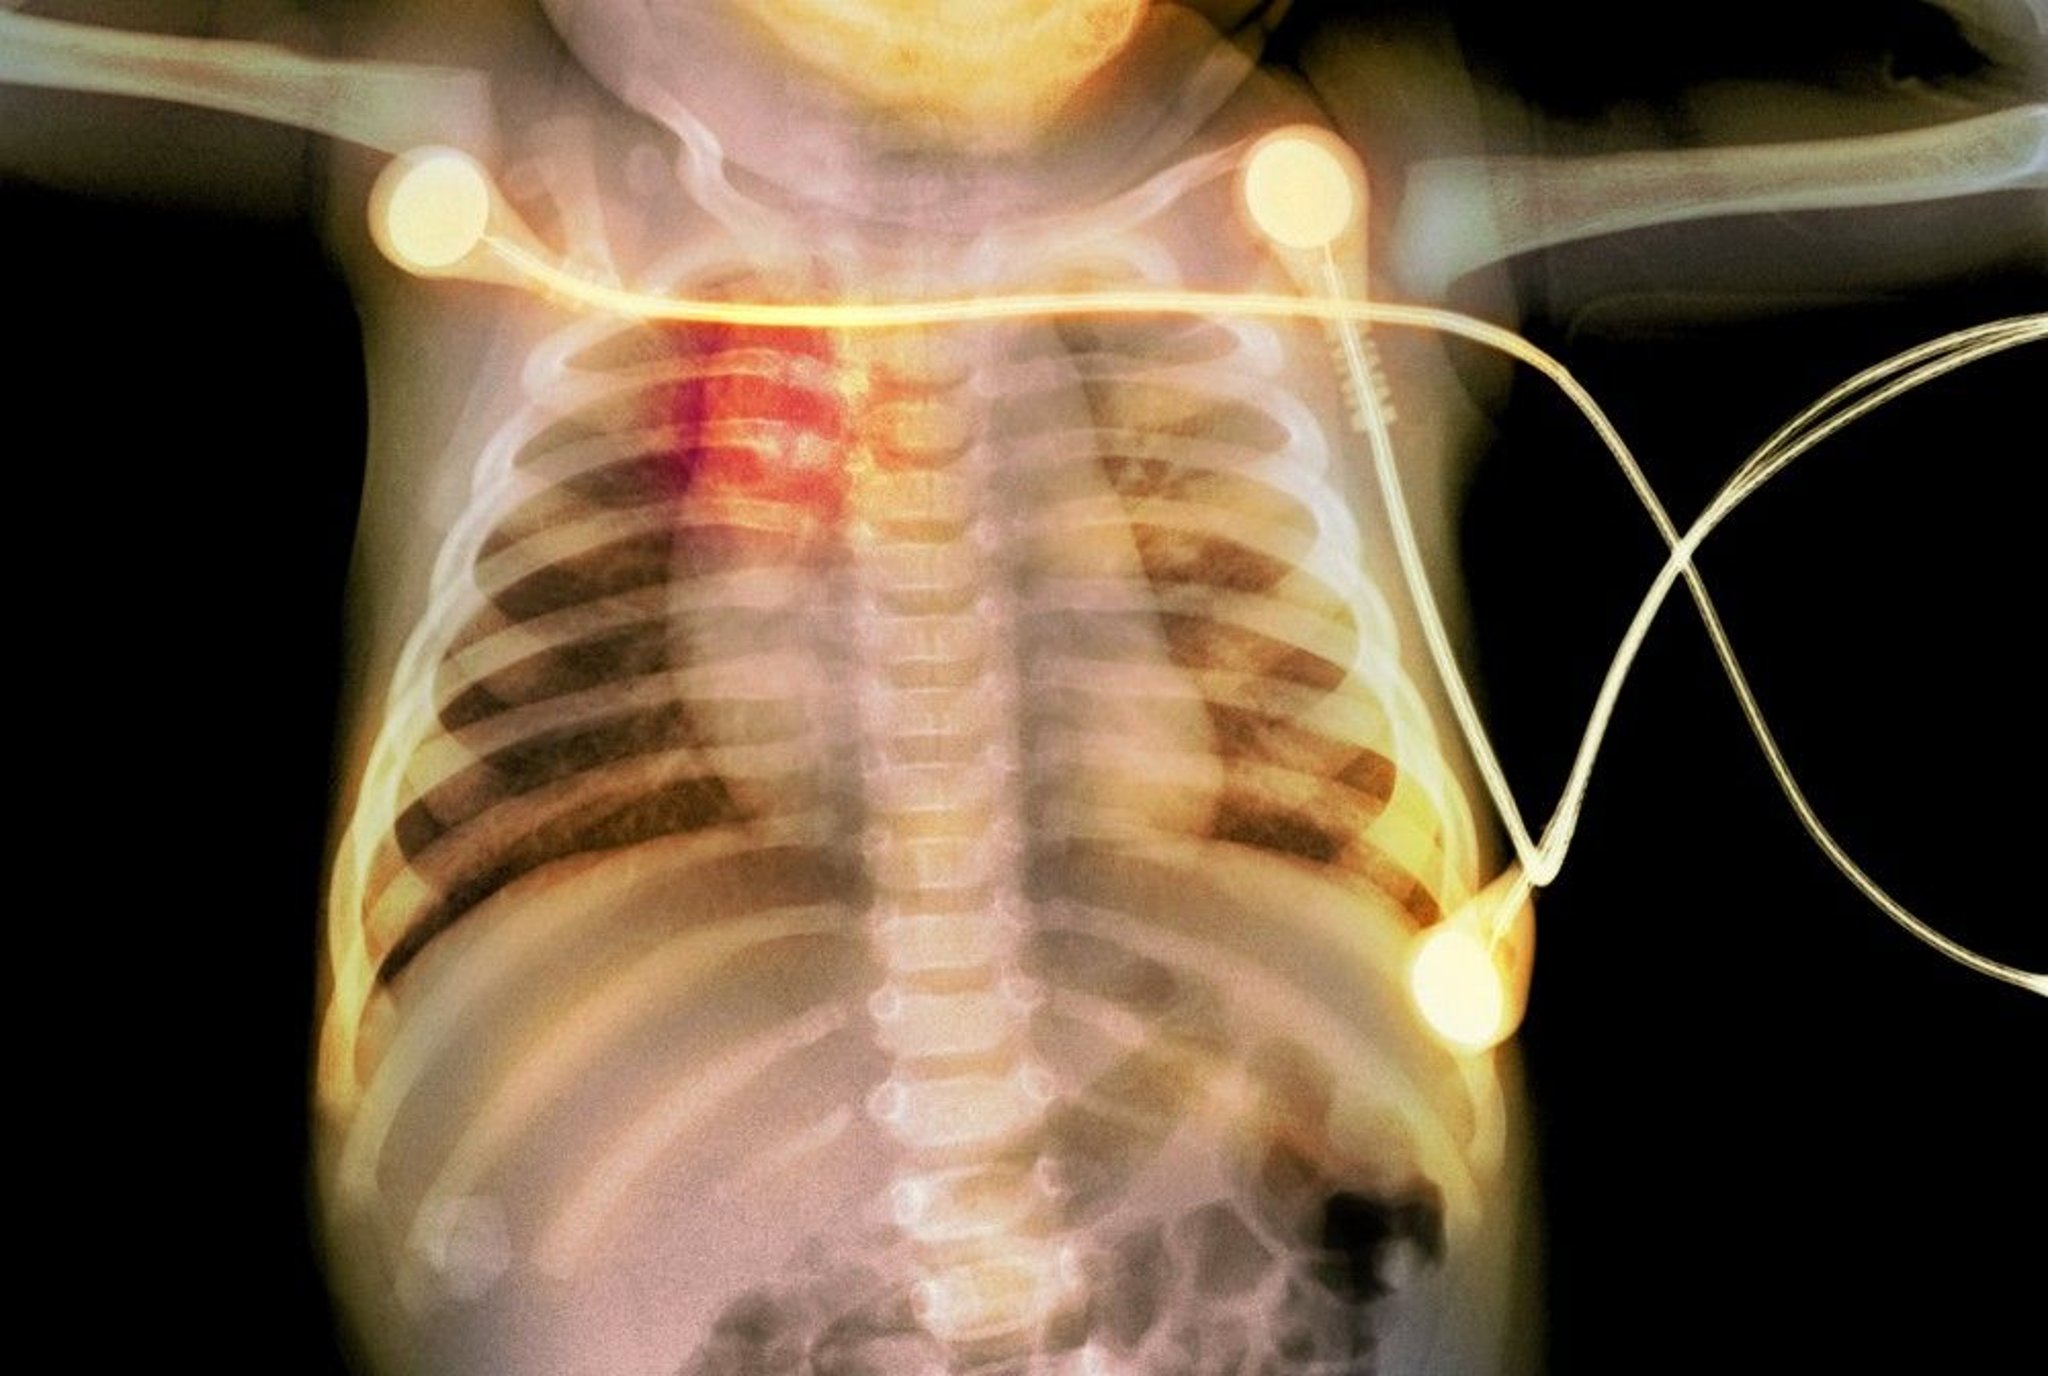

Rib Fractures in an Infant

This radiograph shows rib fractures (highlighted in red) in an infant, suggestive of child abuse.

PHOTOSTOCK-ISRAEL/SCIENCE PHOTO LIBRARY